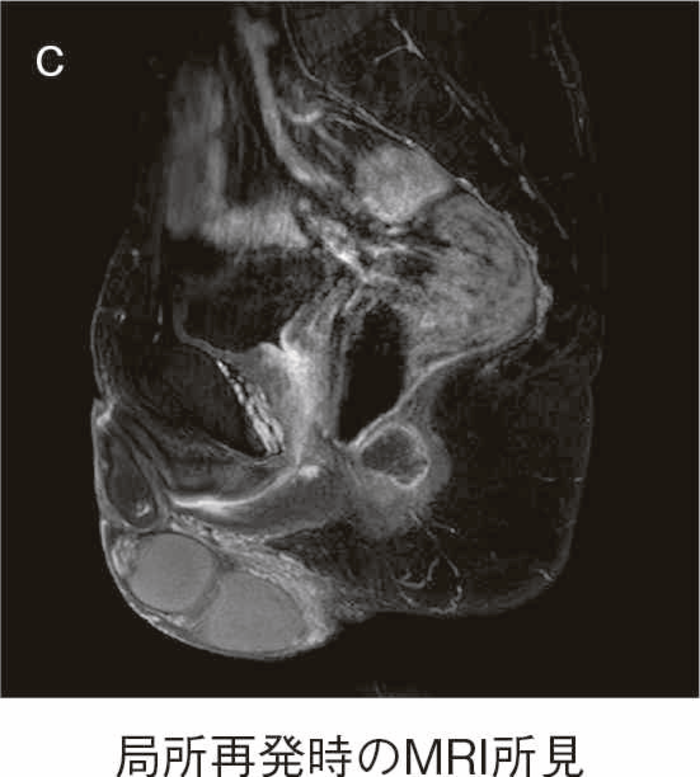

直腸粘膜をすべて切除し,回腸囊と肛門を手縫い吻合する。UCに対しても根治性が高い術式である。図14のように,肛門管粘膜の切除開始ラインは歯状線の肛門側で,肛門陰窩をすべて切除する。切除開始ラインが歯状線よりも口側になり,一部肛門管粘膜(移行帯上皮)を温存させた結果,この残存した粘膜からの発癌を強く示唆する症例報告も存在する2)。また,IAAを行ったにもかかわらず,術後に発癌したという症例報告も存在するが,多くは術後3年以内に発症している症例が多く,術前の直腸癌の局所再発が原因ではないかとの意見が一般的である3)。下部直腸から肛門管にかけて早期癌を合併するような症例では,術後の病理検査で,DM0,RM0であっても図15のように局所再発を生じる可能性もあるので,定期的な画像診断とともに,直腸診を行い,局所再発がないことを確認すべきである4)。

図15 IAA後に局所再発を生じた症例